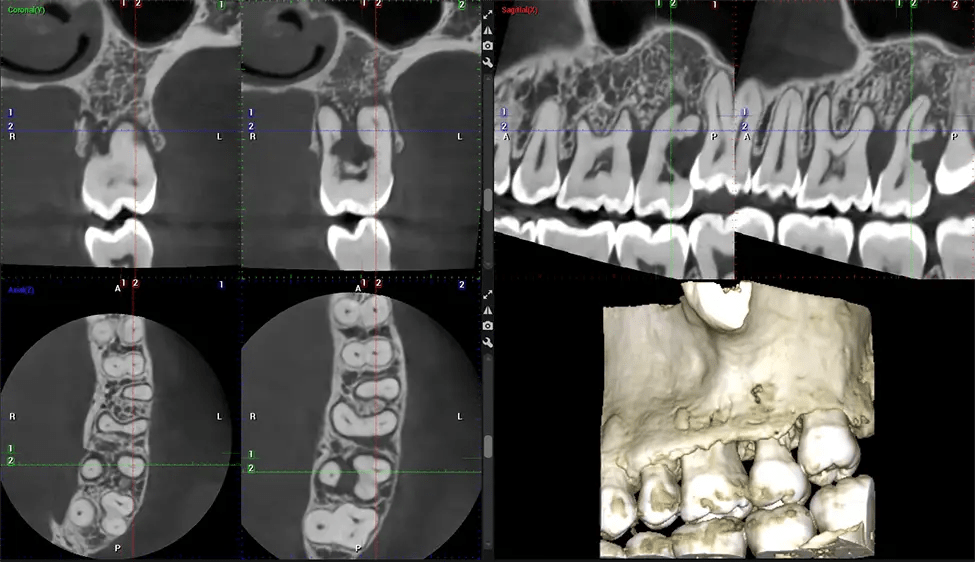

This 3D scan, called cone beam computed tomography, gives your dentist a more complete image of your oral anatomy and disease processes than a traditional X-ray. Unlike conventional X-rays, which capture a 2D image of your mouth from various angles, a 3D scan takes multiple digital X-rays for one image. It provides a complete view of your jaw, teeth, nerves, and soft tissues. This enhanced view allows dentists to detect minor issues not visible in traditional 2D scans, such as impacted wisdom teeth or bone fractures in the sinus cavity.

Another significant benefit is that 3D imaging provides more precise images of your bone structure. These images are more detailed, providing you with a more accurate diagnosis. An accurate diagnosis means better treatment for you.

The patient is first positioned in the CBCT scanner, which typically consists of a rotating arm that houses the X-ray source and a detector. The patient’s head is immobilized to ensure accurate image capture. The X-ray source and detector rotate around the patient’s head, capturing various X-ray images from multiple angles. As the X-ray source rotates, it emits the cone-shaped X-ray beam towards the detector. The detector captures the X-ray images, which are then processed by the CBCT software.

After the scanning process, the captured X-ray images are processed by the CBCT software, which applies algorithms to reconstruct a detailed 3D image of the scanned area. The software compiles these individual X-ray images and creates a digital 3D representation of the patient’s anatomy. The reconstructed 3D CBCT image can be viewed and analyzed by the dentist or radiologist. This image can be manipulated, rotated, and zoomed in or out to examine specific structures and evaluate the patient’s condition.